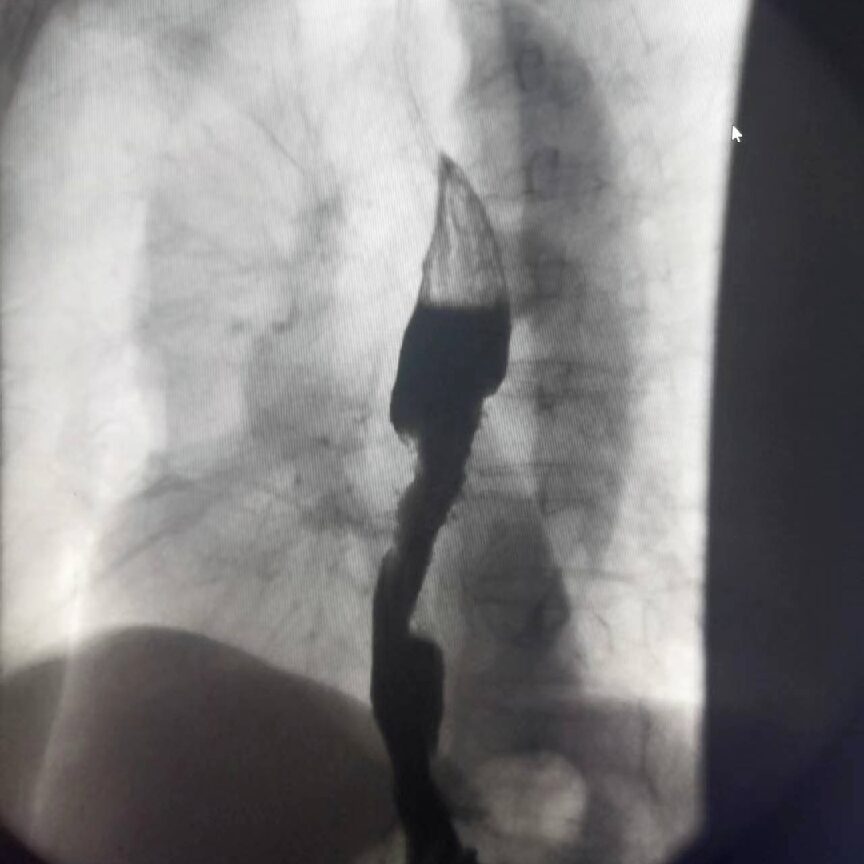

ERCP

Imaging displays effects, and using an endoscope for ERCP operation is a minimally invasive treatment method for removing stones from the intrahepatic bile ducts.